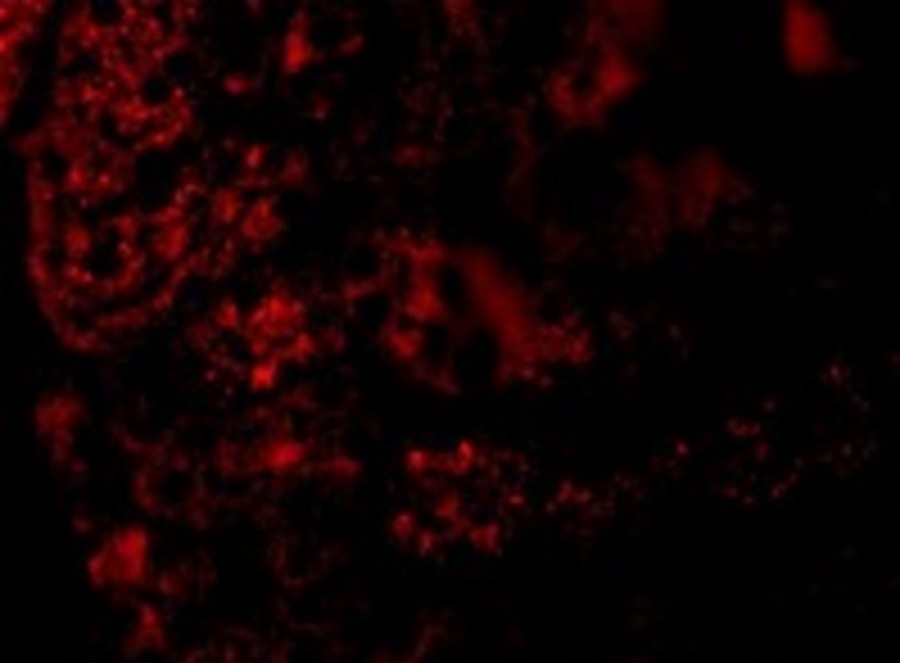

Supportive validation

- Submitted by

- Arigo (provider)

- Main image

- Experimental details

- Immunofluorescence: Mouse Kidney cells stained with ARG55895 anti-AGTR1 / AT1 antibody at 20 µg/ml dilution.